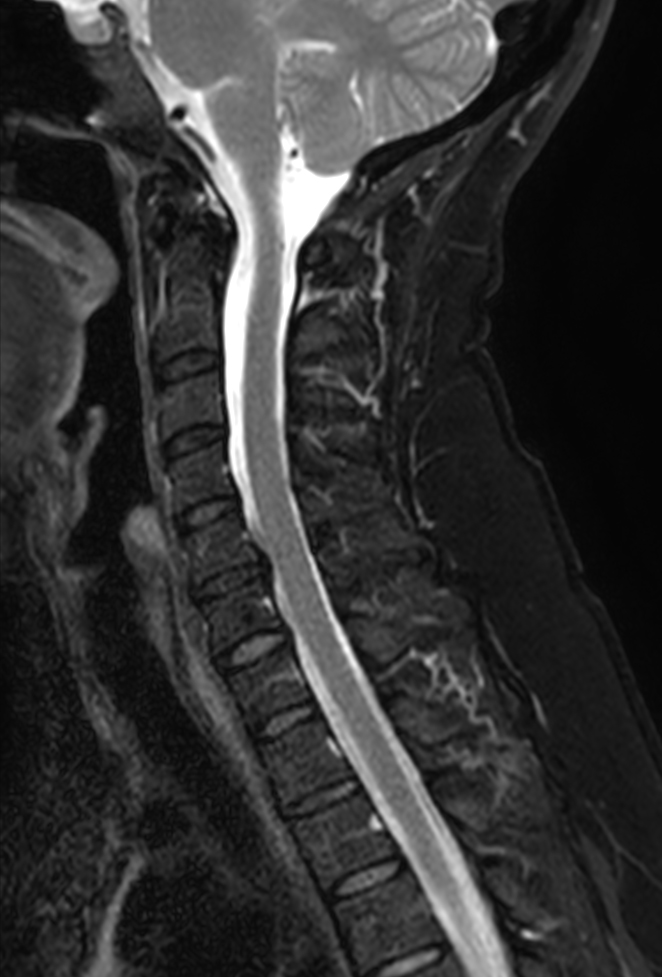

Sagittal T2w TSE